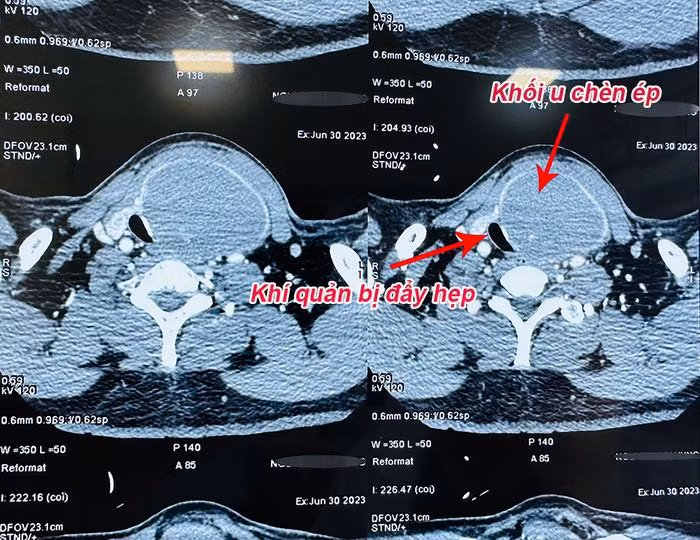

Đến đầu tháng 07/2023, ông H. thấy khó thở, khàn tiếng và nuốt vướng, đi khám lại thì khối u đã có kích thước lên tới 10x10cm, giáp phải cũng có nang kích thước 2x3cm, đè đẩy các cấu trúc xung quanh, đường kính khí quản chỗ hẹp nhất còn 1,8x0,8cm.

Khối u choán diện tích lớn, kéo dài từ sát xương hàm xuống dưới hõm ức, chèn lệch khí quản, chèn vào dây thần kinh thanh quản và cả một phần thực quản. Lúc này, bệnh nhân mới xin được phẫu thuật.